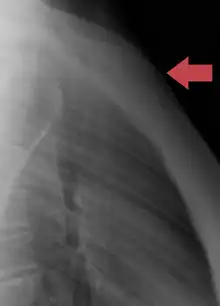

Position of sternum (shown in red). Animation.

Sternum, lateral aspect